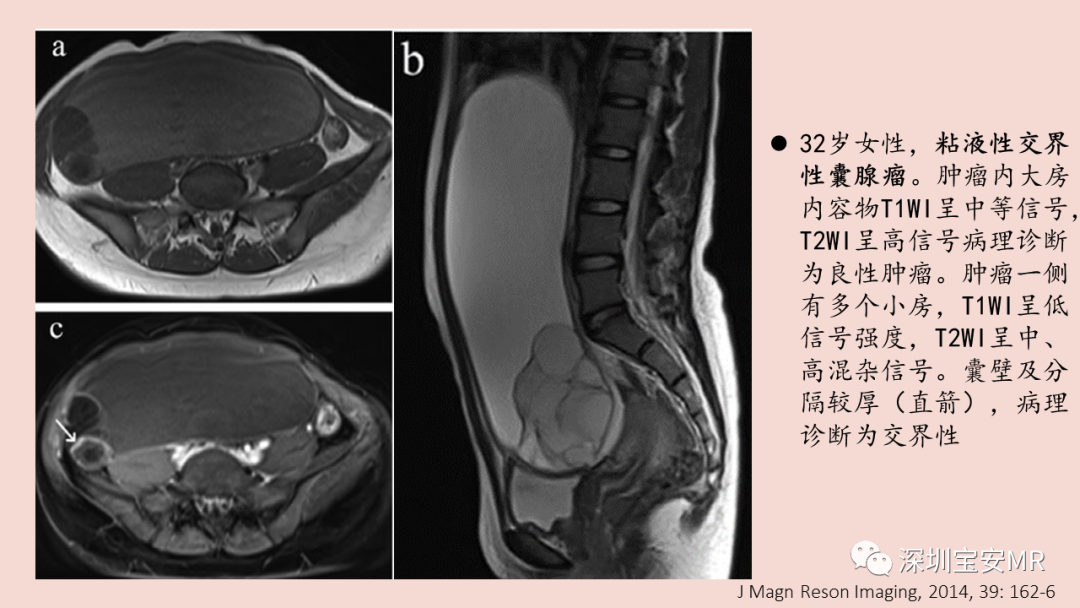

图片